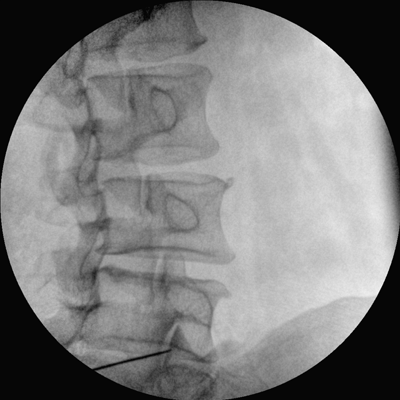

智能化控制系統(tǒng), 讓手術(shù)高效暢捷

四維電動(dòng)運(yùn)動(dòng)控制,平滑定位,使得復(fù)雜角度快速實(shí)現(xiàn)。

專(zhuān)業(yè)的圖像處理系統(tǒng),為您提供高分辨率、高灰階圖像。